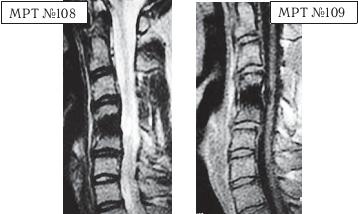

На МРТ № 108 состояние шейного отдела позвоночника пациента через 11 месяцев после дискэктомии с межтеловым спондилодезом в сегменте СIV—СV Наблюдается постхирургическая травма спинного мозга на данном уровне хирургической фрезой, кифозирование физиологического лордоза, стеноз позвоночного канала с блоком ликворных путей.

На МРТ № 109 состояние шейного отдела позвоночника того же пациента через 23 месяца после дискэктомии с межтеловым спондилодезом в сегменте CIV-CV Наблюдается усугубление стеноза (абсолютный стеноз), спондилолистез (смещение вышележащего позвонка по отношению к нижележащему) СII— СIII, секвестрированная грыжа межпозвонкового диска CV—CVI.

На данных снимках наглядно отображается, как подобные операции усугубляют биомеханические нарушения и тем самым способствуют развитию дегенеративно-дистрофического процесса в других сегментах позвоночника. Во время операции грыжу межпозвонкового диска в данном сегменте убрали. Но причины, которые как раз и спровоцировали образование грыжи, а именно биомеханические нарушения (дегенерация выше- и нижележащих межпозвонковых дисков, стеноз, кифоз), как были, так и остались! Несмотря на то что отдалённые последствия этой операции легко прогнозировались и полученный результат, как факт, абсолютно закономерен, подобные операции, к сожалению, как делались, так и делаются и, пожалуй, самое печальное, что и будут делаться дальше.